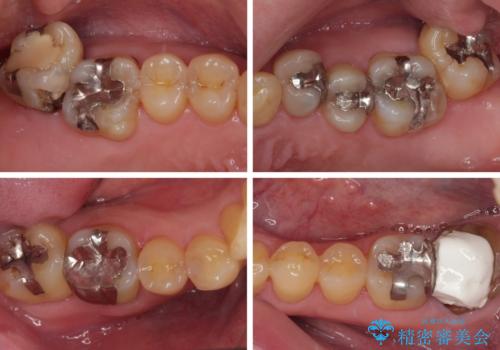

外側に飛び出している歯 部分矯正を用いた奥歯の補綴治療

- 奥歯のむし歯治療を希望して来院された患者様です。

上顎の奥歯は、左右ともに外側に転位しており、特に右上はむし歯の範囲が広く、根管治療も必要な状態でした。

左下の奥歯は状態が非常に悪く、保存は困難と判断されたため、インプラントによる補綴治療が必要でした。

上顎左右の歯をアンカースクリューを用いた部分矯正により位置を修正し、オールセラミッククラウンにて補綴治療を行うこととしました。